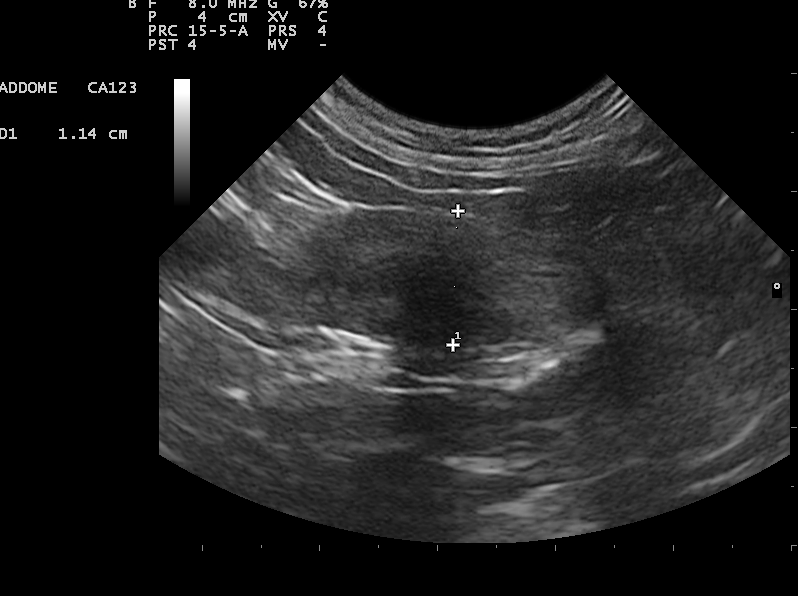

La diagnosi di solito si effettua attraverso un’ecografia addominale, così da riuscire ad evidenziare sia i corpi estranei radio opachi che quelli radio trasparenti (che non si vedrebbero con una radiografia). E poi?

L’ecografia ci permette anche di valutare dimensioni e forme dei corpi estranei, perché se sono nello stomaco è possibile rimuoverli con una gastroscopia, ma per essere eliminati con questa tecnica devono avere dimensioni e consistenza tali da poter essere afferrati con la pinza e trascinati a ritroso attraverso l’esofago e non devono essere appuntiti altrimenti si rischia di lesionare l’esofago estraendoli.